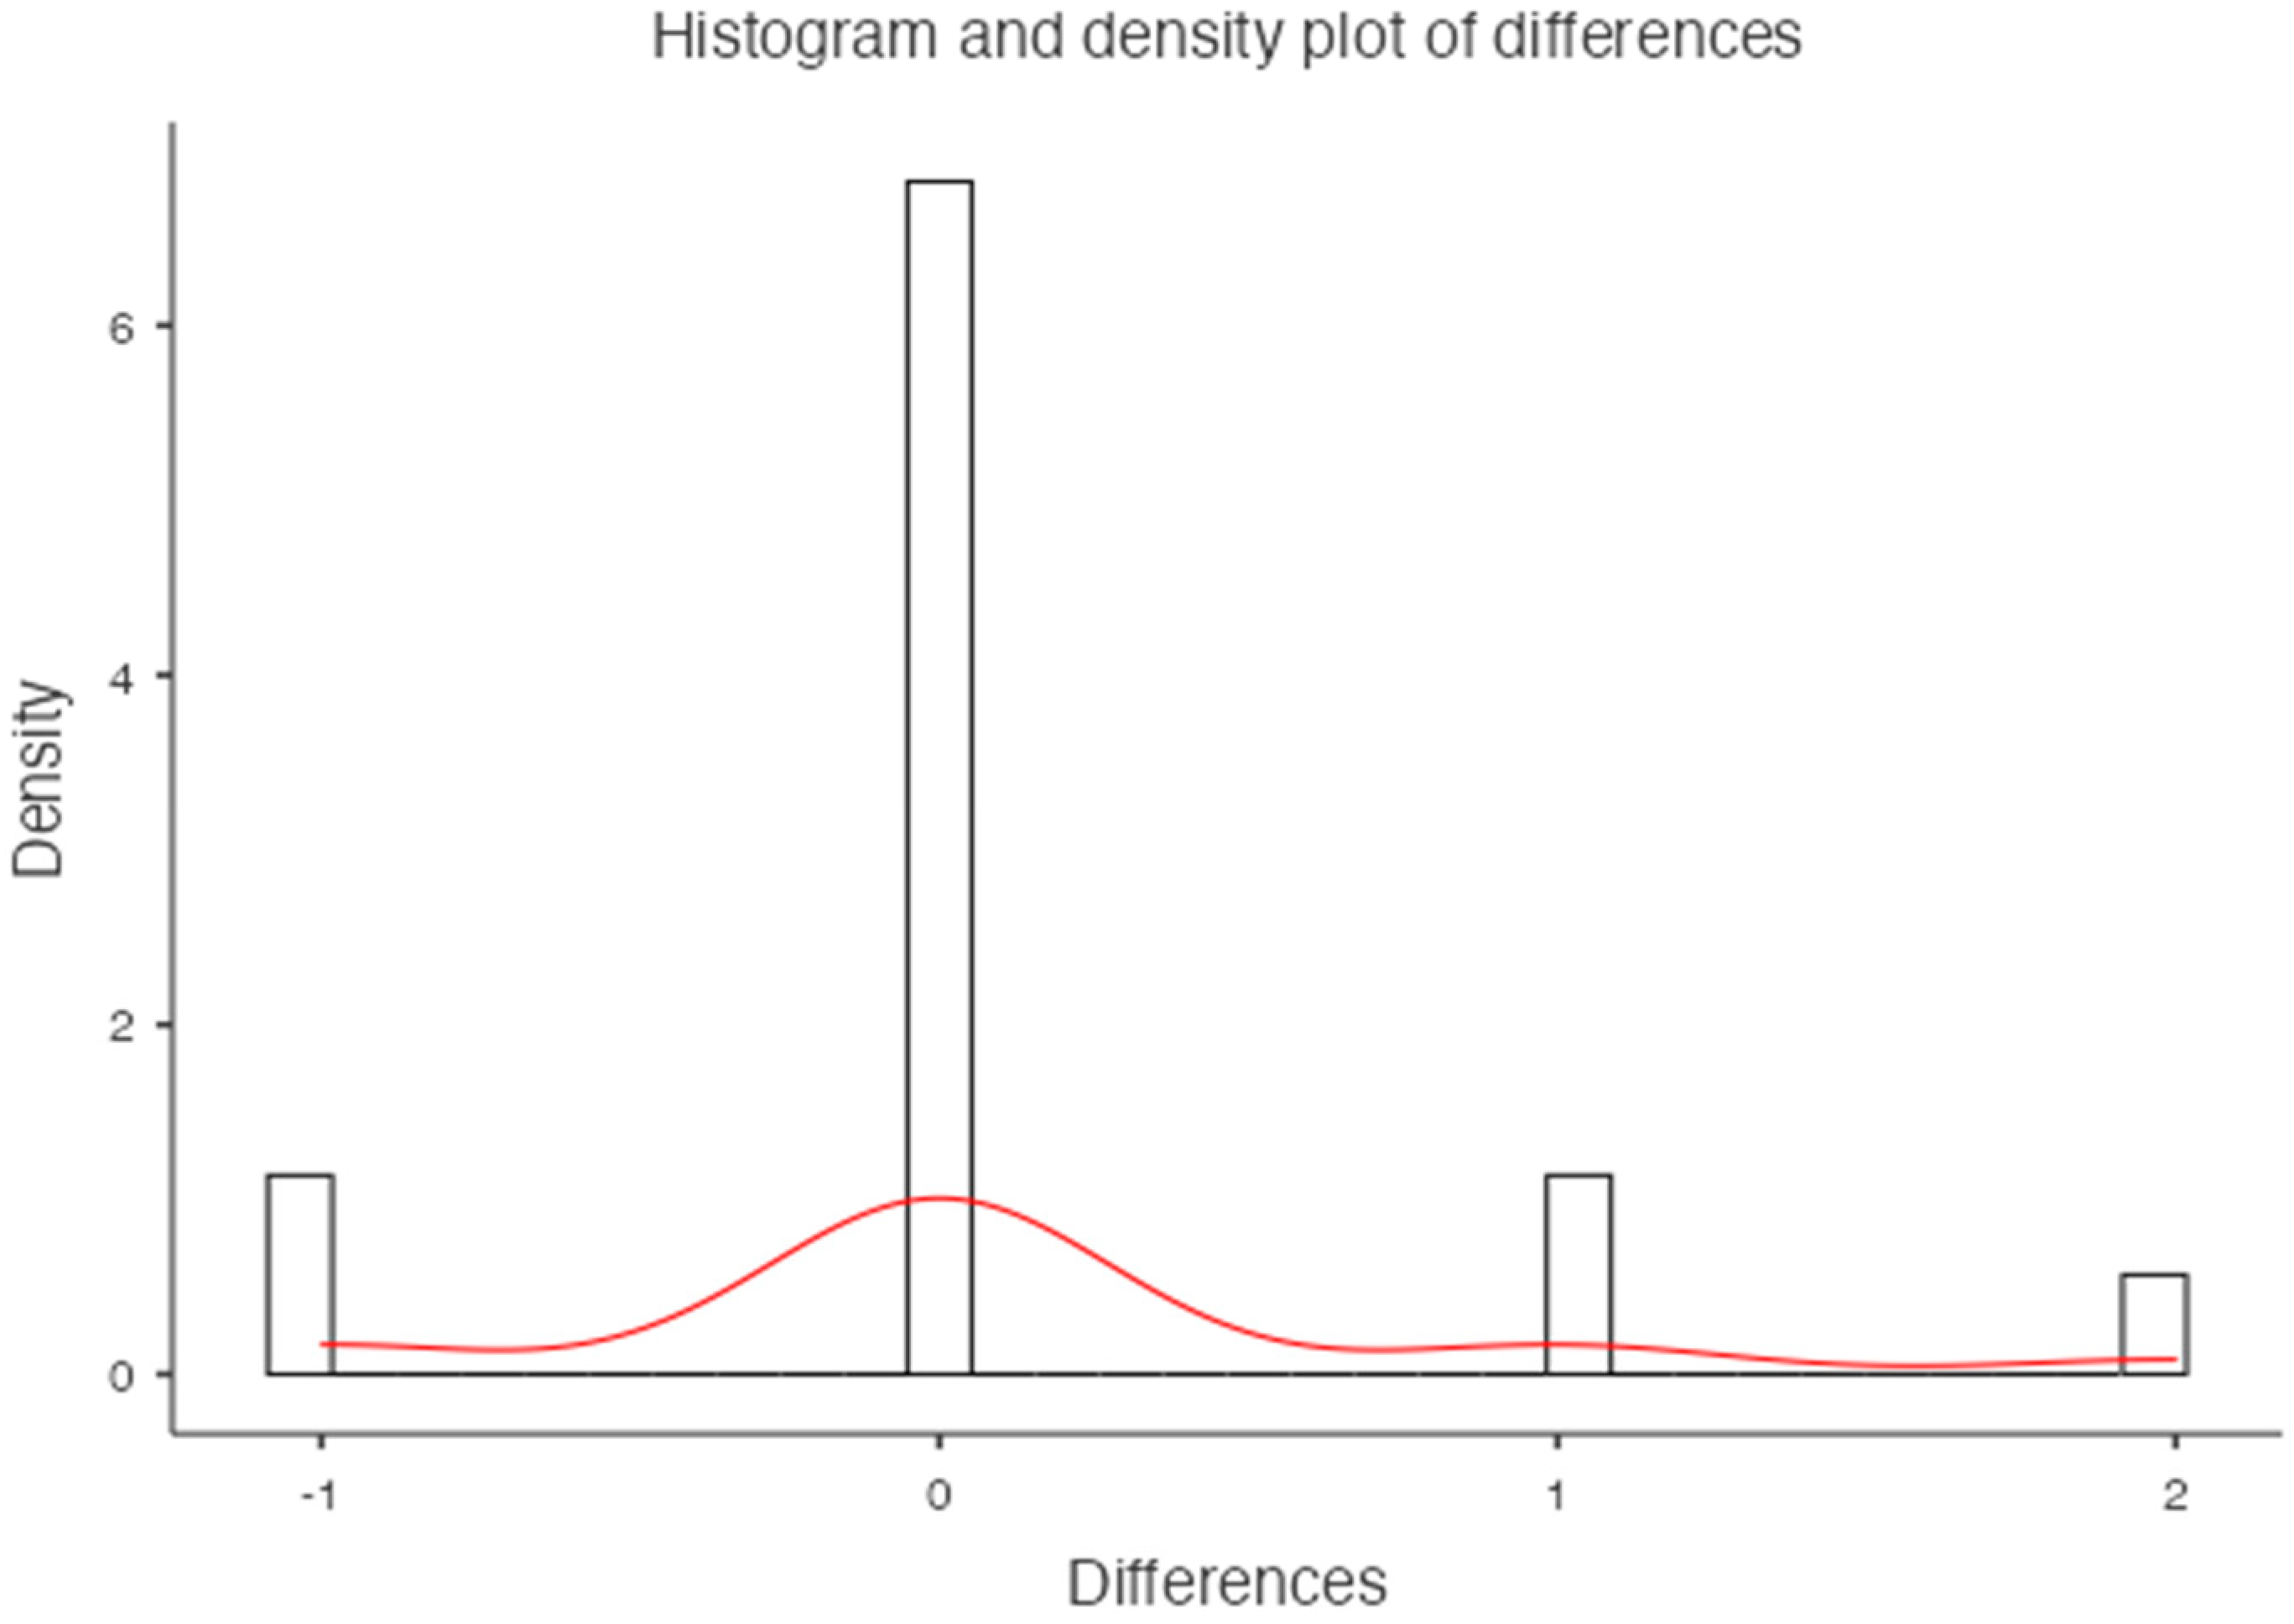

3. Results